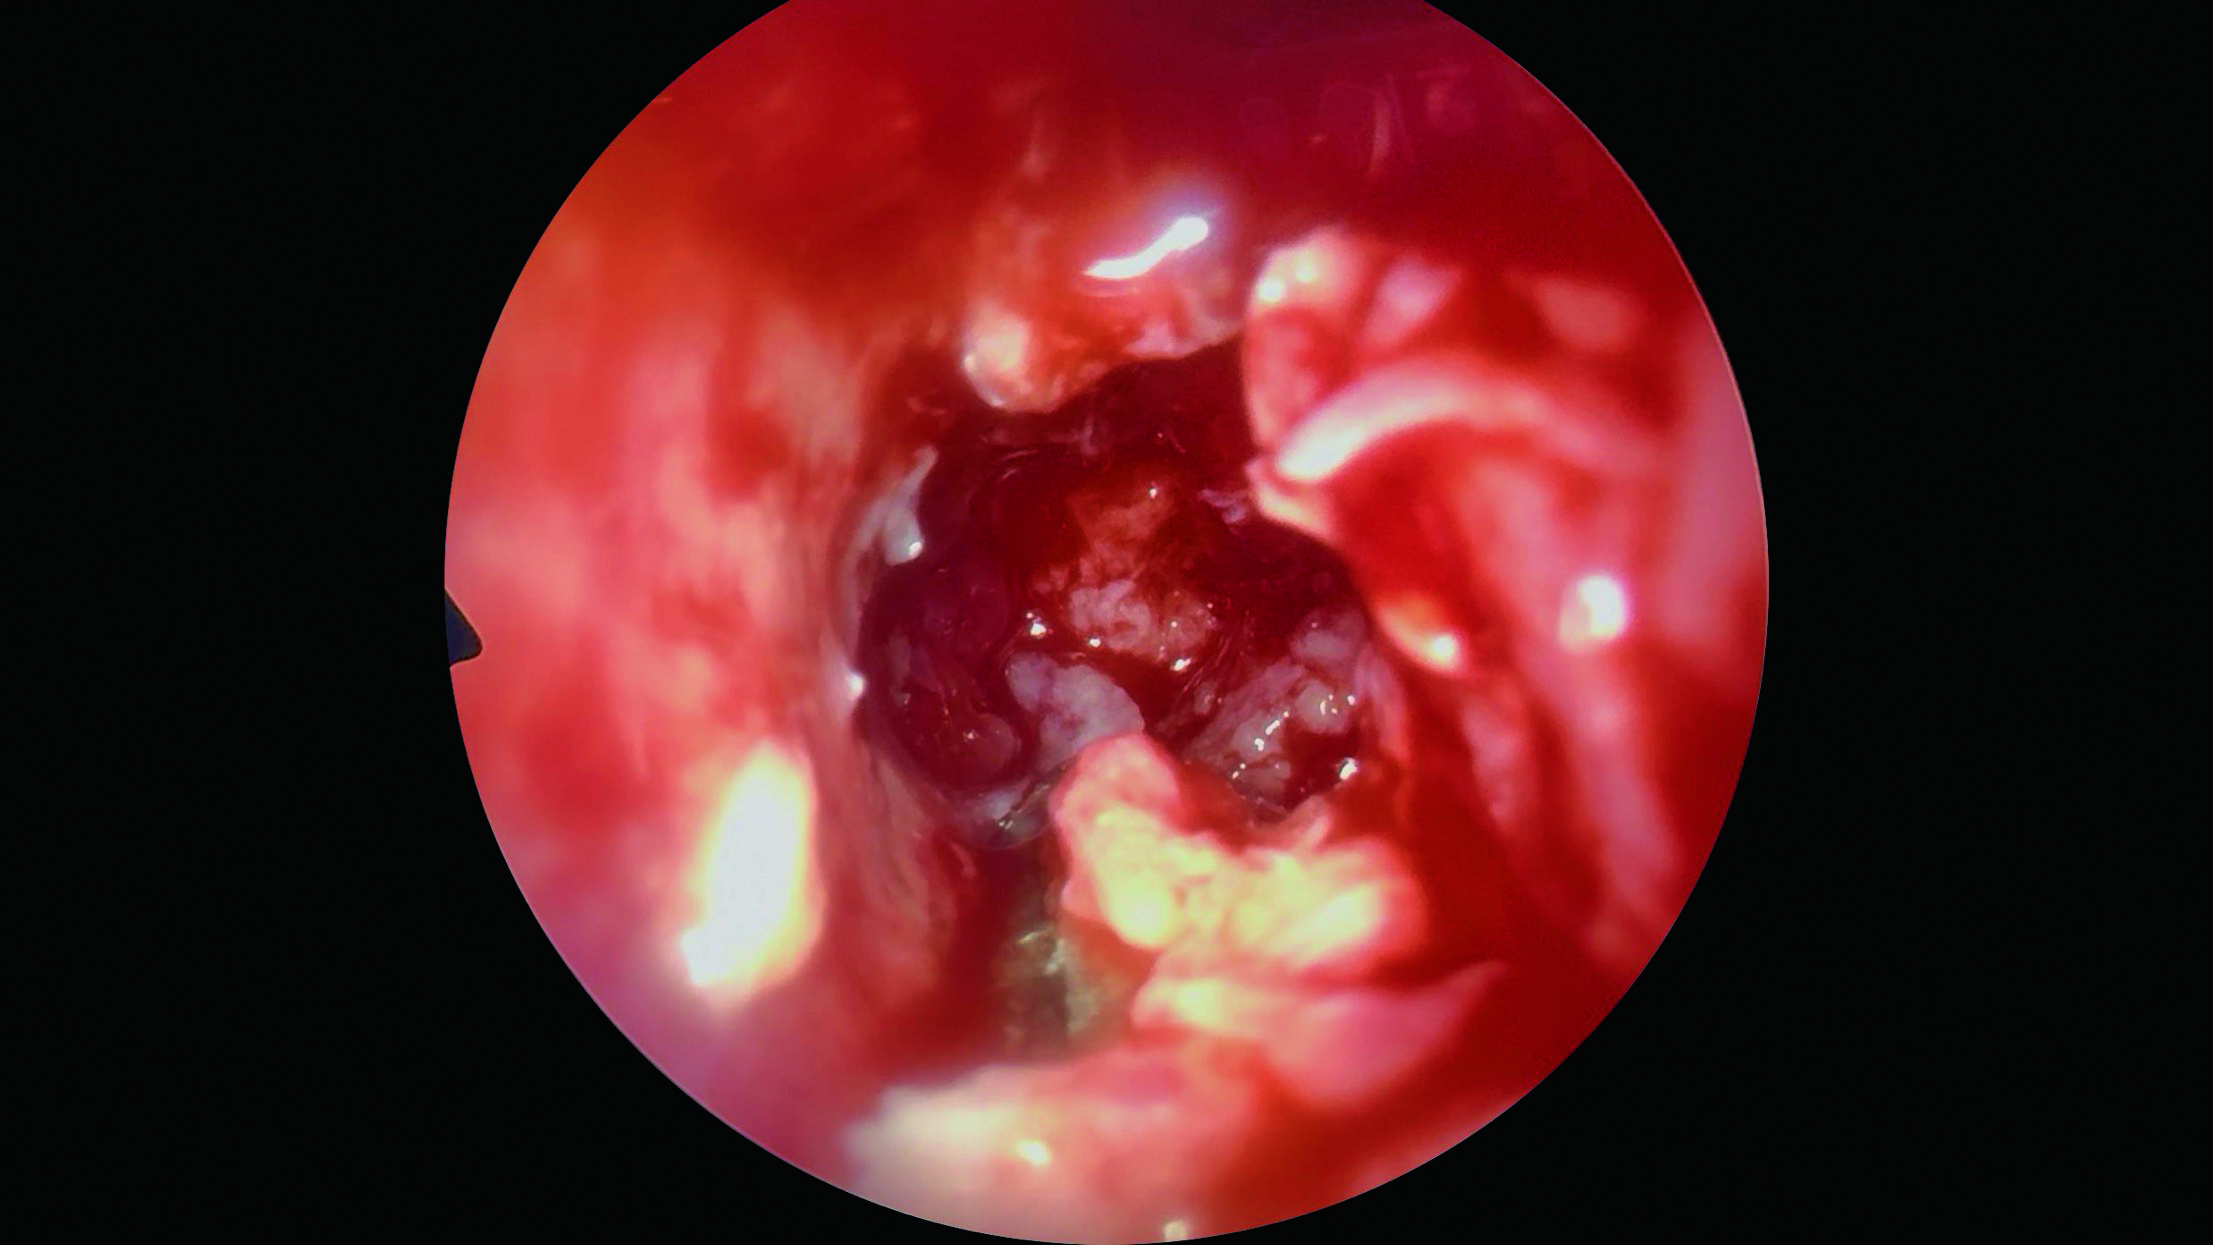

При проведении мультиспиральной компьютерной томографии (МСКТ) головы, шеи и органов грудной клетки с контрастным усилением выявлено массивное остеолитическое опухолевое образование основной пазухи, тела и крыльев клиновидной кости слева, ячеек решетчатой кости с деструкцией костных структур и интракраниальным распространением в область турецкого седла, средней черепной ямки и конуса левой глазницы. Также отмечено вовлечение левой внутренней сонной артерии и левого зрительного нерва в структуру опухоли (рисунок 1). По данным МСКТ органов брюшной полости выявлены единичные микрокальцинаты в паренхиме обеих почек, увеличенных лимфатических узлов не обнаружено. Результаты миелограммы и ликворограммы не выявили признаков специфического поражения. Выполнена трансназальная эндоскопическая биопсия опухоли (рисунок 2).

Рисунок 2

Внешний вид опухоли при трансназальной эндоскопической биопсии образования

Figure 2

The appearance of the tumor during a transnasal endoscopic biopsy